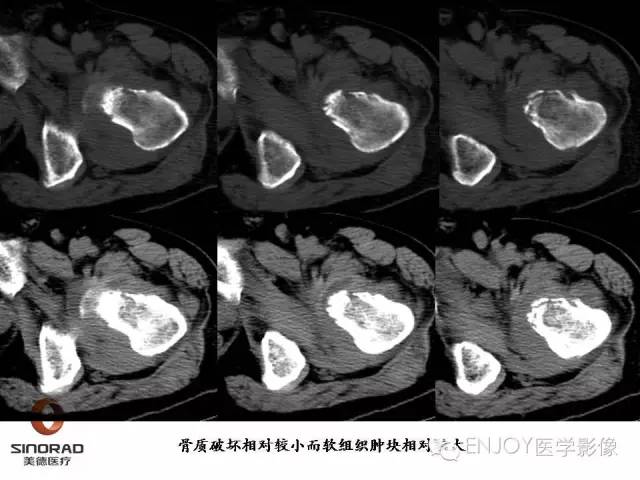

【病例】右侧股骨多形性肉瘤1例X线及MR影像表现

多形性肉瘤(以往称为:恶性纤维组织细胞瘤)